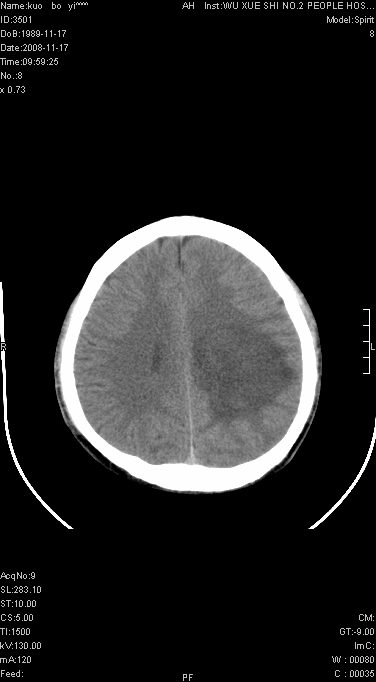

给我的整体感觉 以脑炎性病变可能大,结合实验室检查以除外结核性病变

以脑炎性病变可能大,结合实验室检查以除外结核性病变

年龄小,病程短,不支持脑肿瘤及转移瘤,首先考虑炎症及结核。

在北京天坛医院治疗考虑寄生虫感.明显好转